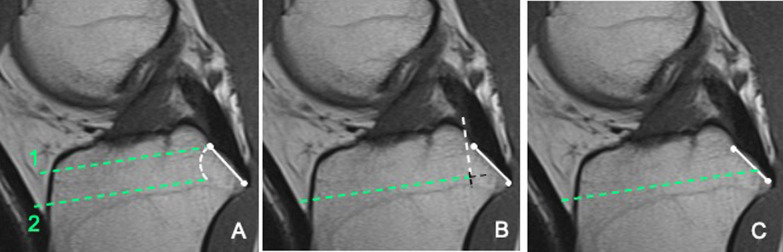

Materials and methods: Patients undergoing cruciate retaining total knee arthroplasty were recruited in a prospective, randomized, controlled trial. In 25 patients (group 1) the tibial cut was performed using a double tibial cut technique; in 25 (group 2) and 25 (group 3) patients, the bone island and en bloc resection techniques were performed, respectively. Posterior cruciate ligament integrity and femoral rollback were assessed at the end of surgery. The Oxford Knee Score, WOMAC score and range of motion were assessed postoperatively.

Results: Posterior cruciate ligament was completely preserved in 92% of patients in group 1 and in 64% in group 2 and 3, respectively (p = 0.03). The Oxford Knee Score and WOMAC scores did not differ between groups (p = 0.4). The mean knee flexion was 126.4°, 121.5° and 123.9° in groups 1, 2 and 3, respectively (p = 0.04). The femoral rollback at 120° flexion was 80.7%, 72.2% and 75.4% in groups 1, 2 and 3, respectively (p = 0.01).

Conclusions: The double cut technique preserves the posterior cruciate ligament at significantly higher rates than the bone island or en bloc resection techniques. Better posterior cruciate ligament preservation may improve the femoral rollback and knee flexion.